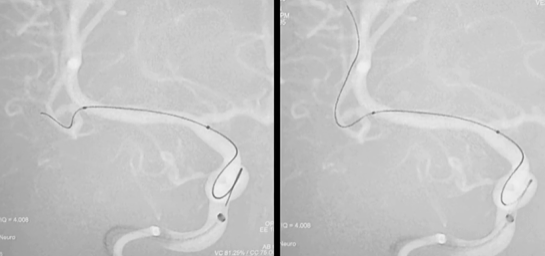

3. 通路搭建,导管到位

微导丝超选、支架导管到位

4. 致密填塞,稳定成篮

栓塞导管到位、弹簧圈逐步填塞

5. 支架释放,精准贴壁

支架释放

6. 警报解除,回归日常

术后DSA示:动脉瘤完全栓塞,瘤腔内未见造影剂充盈,载瘤动脉通畅